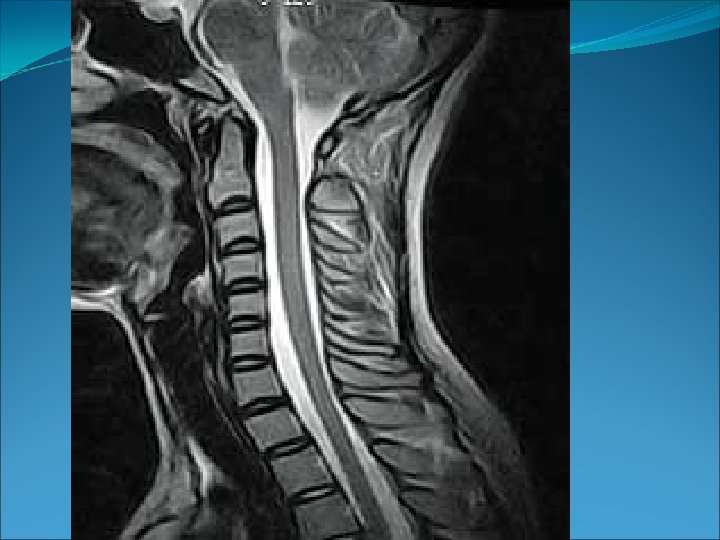

• Plano transversal, horizontal o axial: es un plano horizontal que divide el cuerpo en una parte superior y otra inferior. 6. Eje transversal.